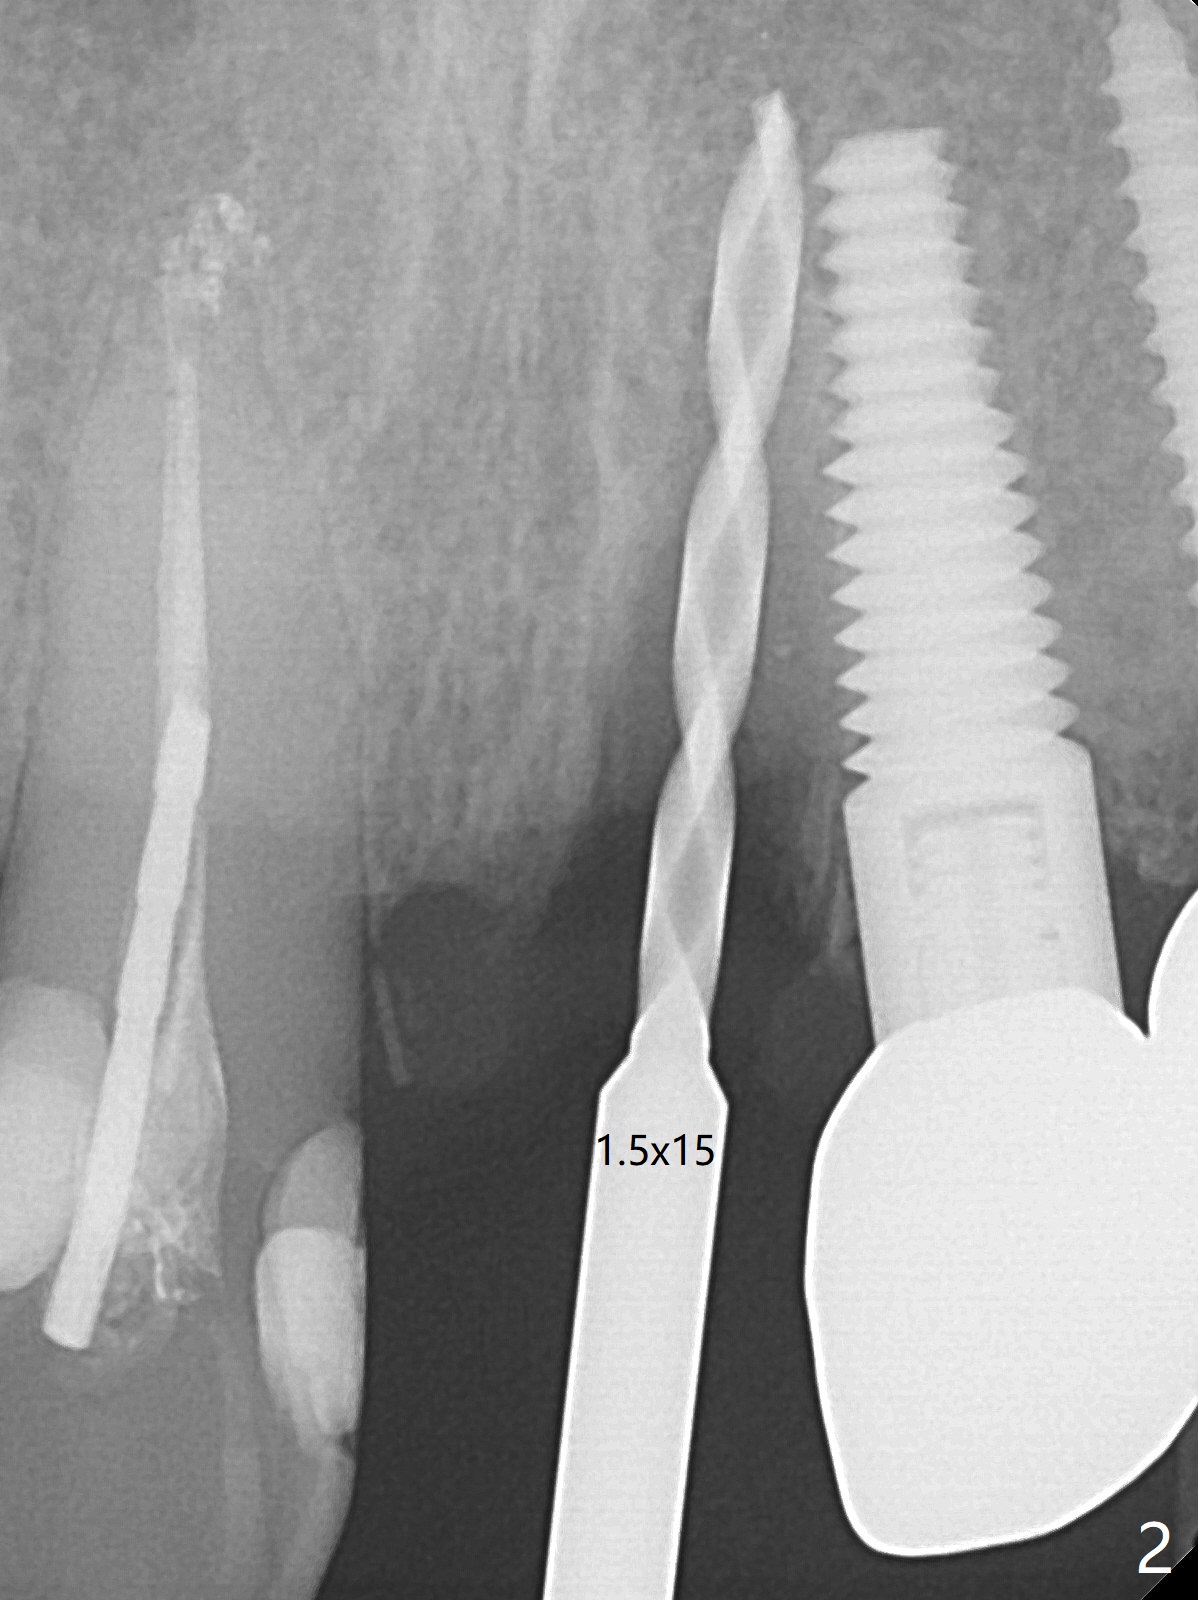

徒手种植不准确,需要反复调整,例如,为了避免接近侧切牙植体,中切牙钻洞开始于牙槽窝腭侧骨壁近中,结果接近切牙管(图一:红虚线),然后使用Lindamann bur移动钻洞,结果又太接近侧切牙(图二)。最后使用2毫米钻头试图改变钻洞方向,结果基台太接近侧切牙牙冠(图三)。而导板植入快,利索。 植入皮质骨骨粉(图四:*)后,制作临时牙冠。大约术后11天临时牙冠脱落(可能基台太短),病人没有及时复位,4天后牙槽窝愈合,可能变小,牙冠就位有些困难,造成颊侧牙龈发白(图五)。一周后牙冠又脱落,衬里后(图六:*)颊侧牙龈又显得饱满。